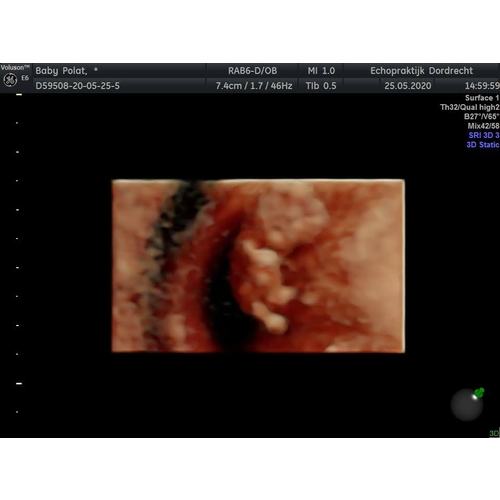

Mijn gynaecoloog heeft van een van de twee kindjes in m'n buik een 3D echo kunnen maken. Het andere kindje zat met de rug naar voor dus daar kon ze geen mooi beeld van nemen.

Mijn gynaecoloog heeft van een van de twee kindjes in m'n buik een 3D echo ...